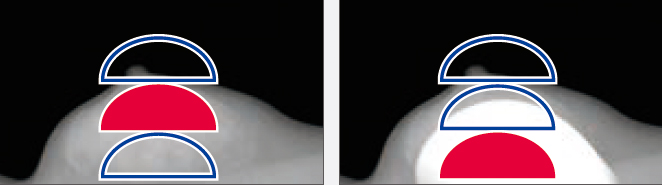

AMULET Innovality utiliza um detector de tela plana de conversão direta feito de selênio amorfo (a-Se) que exibe excelente eficiência de conversão no espectro de raios X mamográficos. O detector HCP (Padrão de fechamento hexagonal) coleta eficientemente sinais elétricos convertidos dos raios X para obter alta resolução e baixo ruído. Este design exclusivo possibilita a realização de uma DQE (Determinação do rendimento quântico) maior do que com a matriz de pixels quadrados de painéis TFT convencionais. Com as informações coletadas pelo detector HCP, a AMULET Innovality cria imagens de alta definição com um tamanho de pixel de 50 μm; o melhor disponível com um detector de conversão direta.

Pixel convencional quadrado

Pixel hexagonal do AMULET Innovality